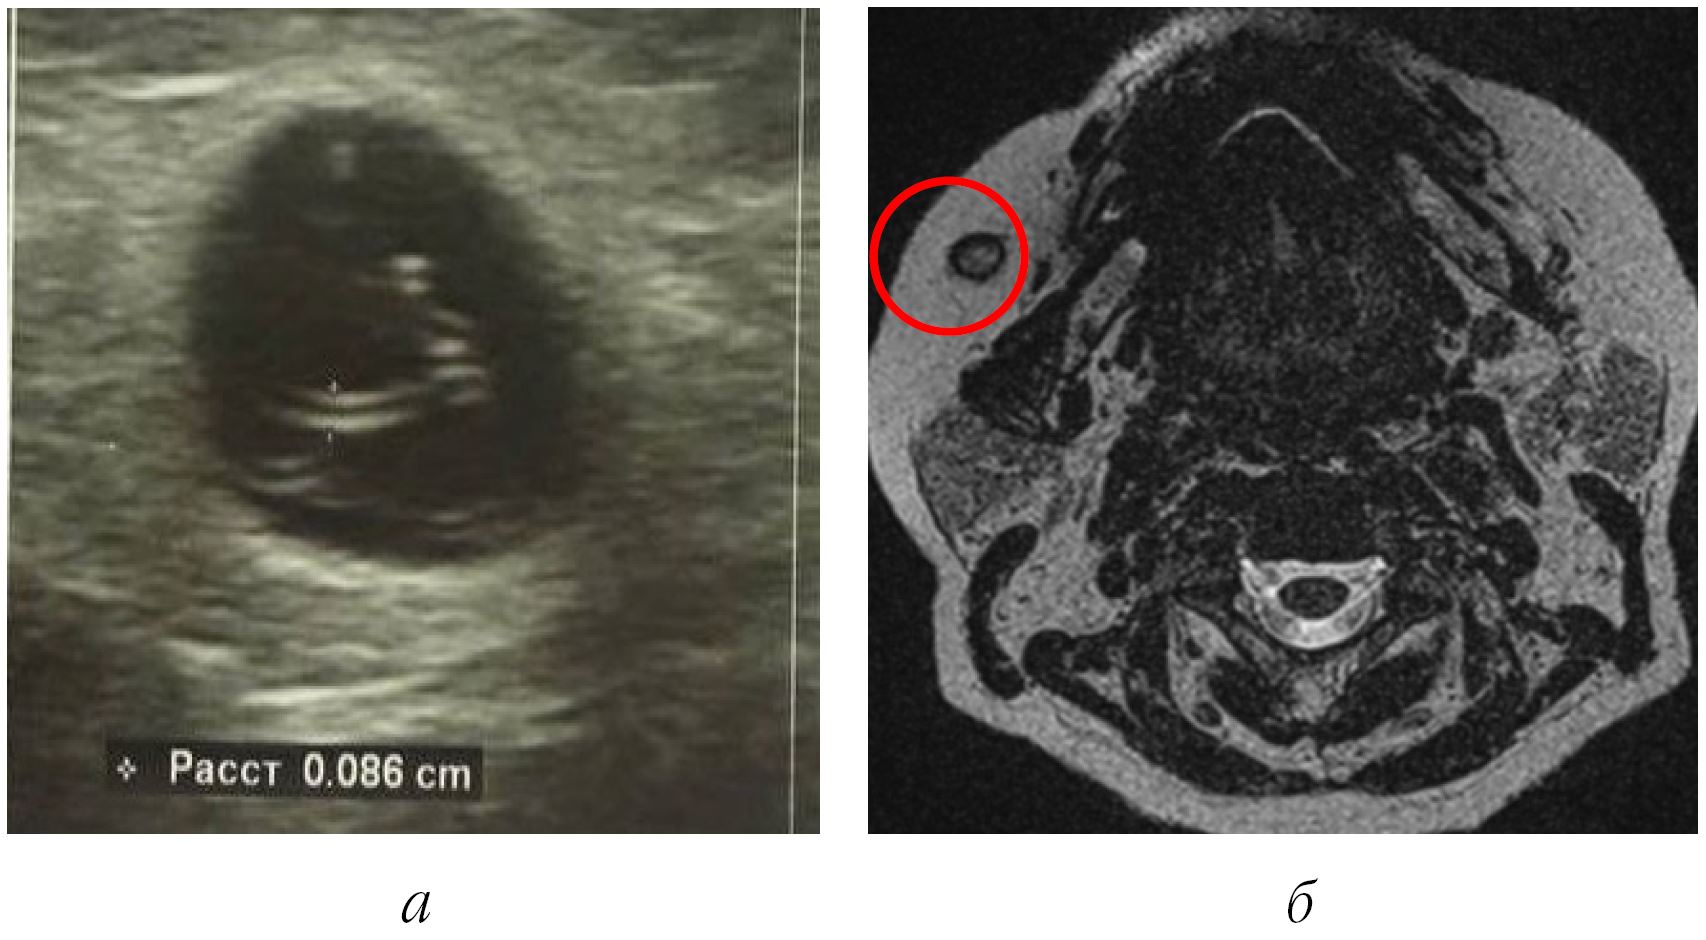

По результатам выполненных УЗИ (рис. 4, а) констатирована следующая картина: шаровидное анэхогенное образование неоднородной структуры с выраженной эхогенной капсулой. В полости определяются подвижные структуры, трубчатые, с диаметром до 0,8 мм, с четкими контурами, что во многом соответствует описанию живого гельминта в капсуле. По данным МРТ-картины дано заключение о наличии инкапсулированного полостного образования в мягких тканях (рис. 4, б).

Рис. 4. Результаты дополнительных (лучевых) методов исследования: а ‒ УЗ-картина инкапсулированной формы дирофиляриоза; б ‒ МРТ-картина инкапсулированной формы дирофиляриоза с локализацией капсулы в мягких тканях щечной области справа